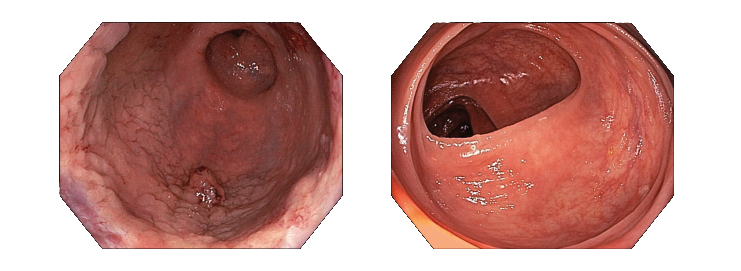

- Технология визуализации в узком спектре NBI, использующая свет определенной длины волны для получения яркого и контрастного изображения структуры слизистой и кровеносных сосудов. NBI — лидер эндоскопического рынка по ранней диагностике рака и других патологических состояний. Узкоспектральная визуализация позволяет диагностировать патоморфологические изменения в тканях даже в случаях, когда осмотр в классическом белом свете не дает результатов.

- Изображение в формате HDTV для максимальной детализации морфологических структур и цветопередачи тканей толстой кишки.

- Широкий угол обзора 170° для оптимального осмотра слизистой без необходимости перемещения дистальной части эндоскопа.